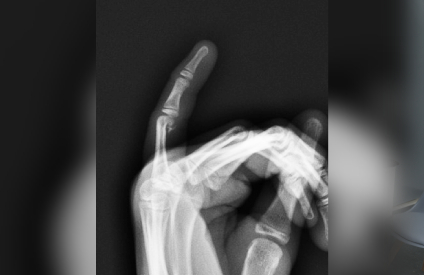

- Multiple View Options for Better Analysis

Our digital X-ray services are essential for diagnosing various orthopaedic conditions, monitoring healing progress, and planning treatments. We use this technology for fracture detection, joint assessments, and pre-operative planning, ensuring precise and effective care for our patients.